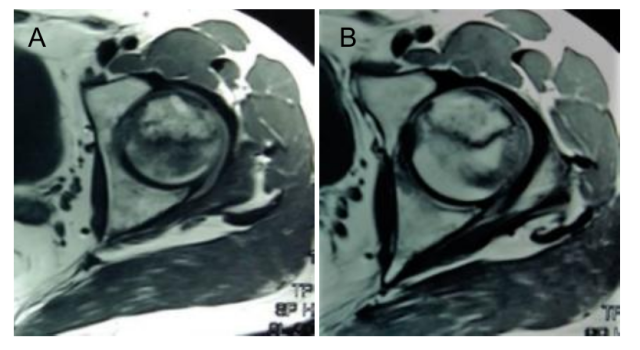

图A:X射线片为正位股骨头,股骨头内不规则高密度影;

此外,MRI片上坏死面积较术前明显减小,治疗前坏死面积为(31.0±5.3)mm2,治疗后为(24.3±3.5)mm2,具有差别意义。